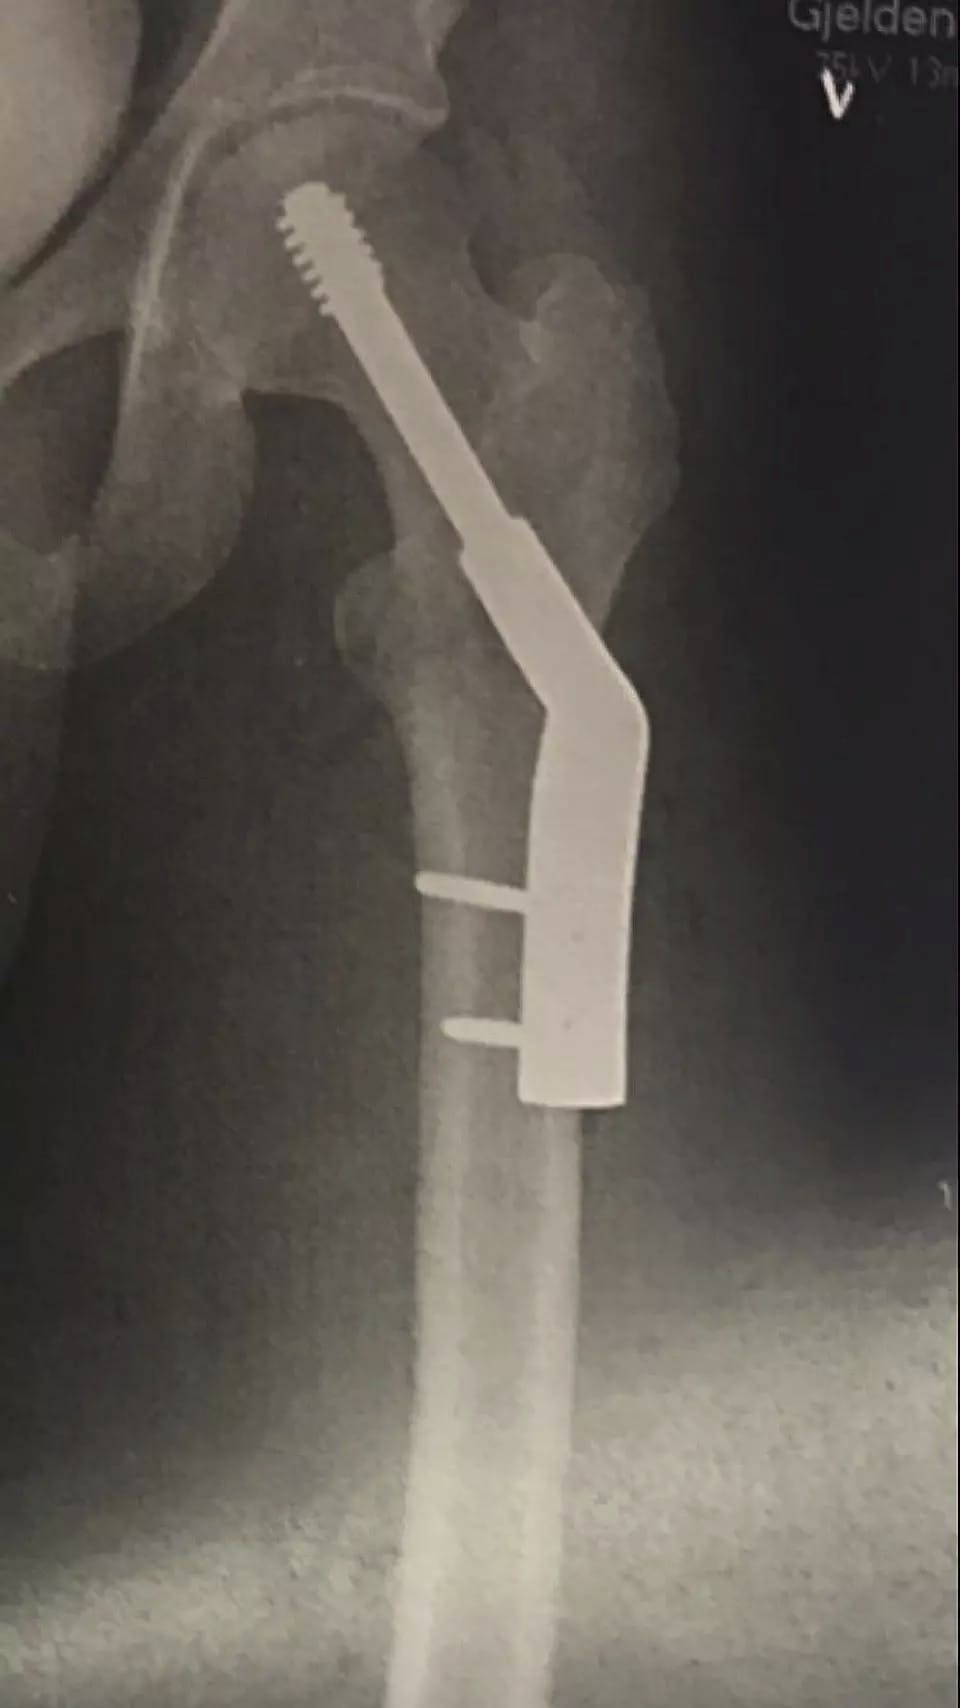

Lårbenet var brækket. Smerterne var ulidelige.

Benet var endda ødelagt så slemt, at det krævede en operation og månedsvis med benhård genoptræning for at komme til at virke nogenlunde almindeligt igen.

Om den semiprofessionelle rytter nogensinde kunne holde ud at cykle på seriøst plan igen var ikke sikkert.